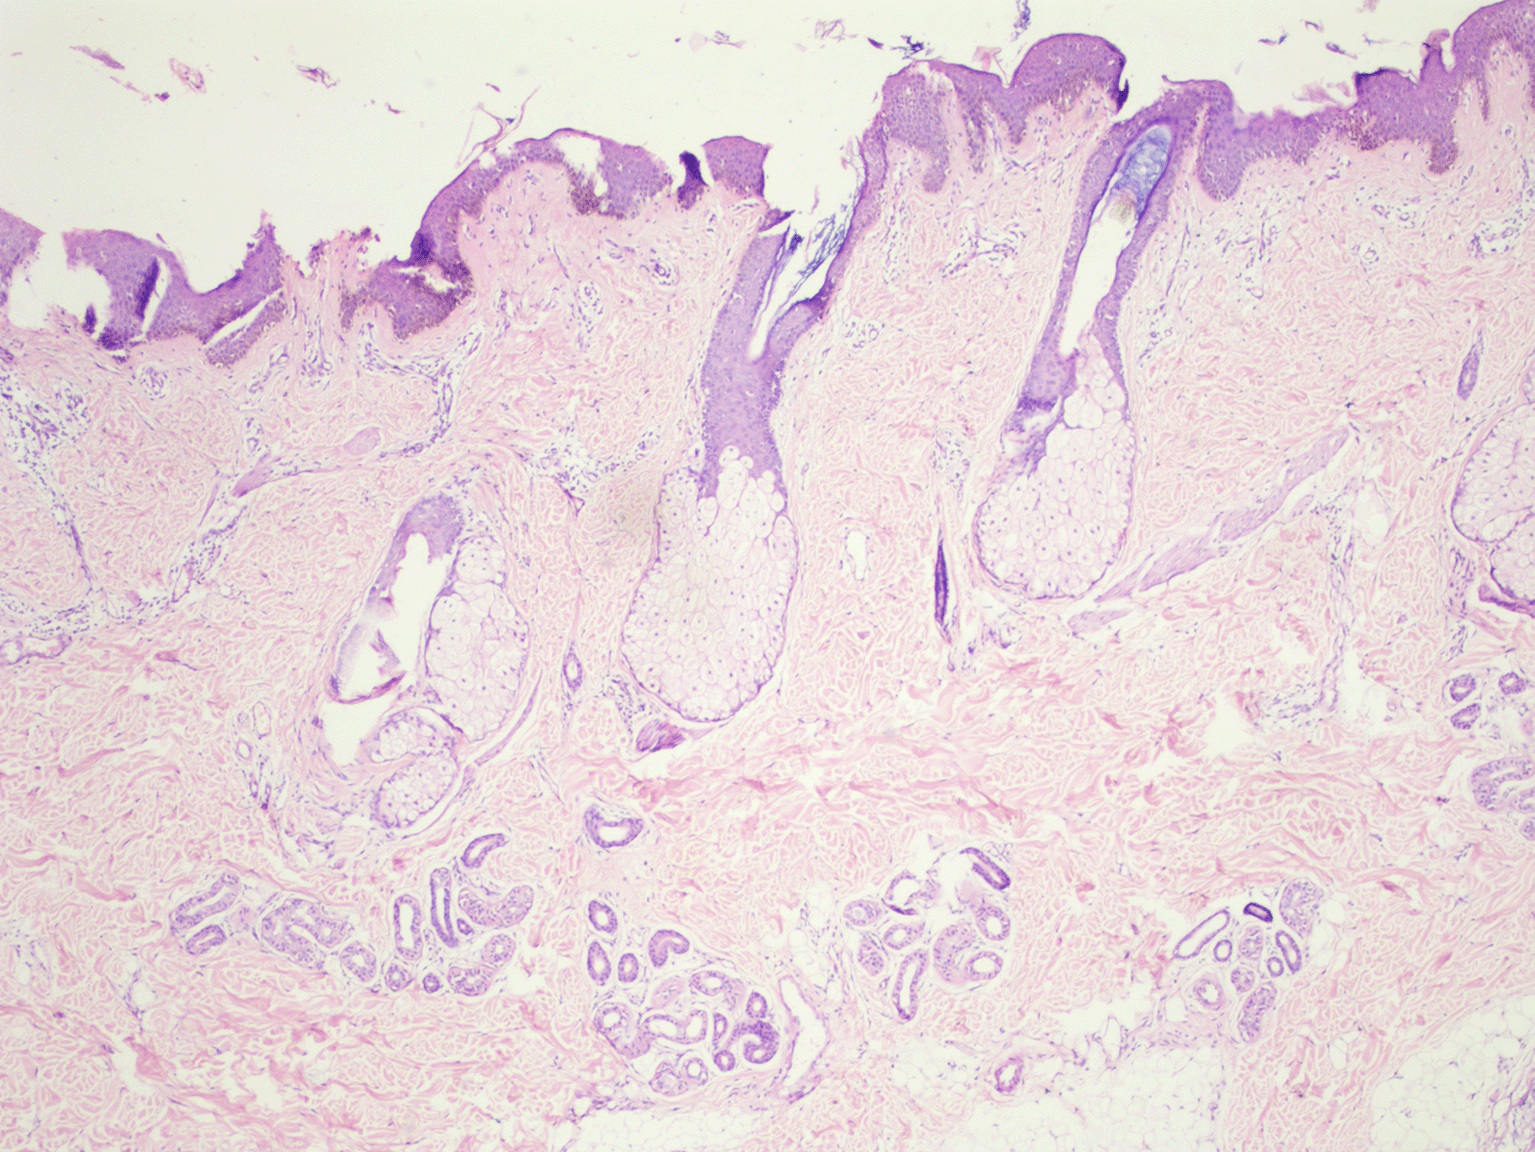

On cutaneous examination, a well-demarcated hyperpigmented verrucous plaque with a size of 8 × 4 cm was present on the frontal area of the scalp extending down to involve the forehead and a 7 × 3 cm plaque was present on the temporoparietal area and left preauricular area [Figure 1]. Based on the patient’s medical history and physical examination, the possible differential diagnoses were identified as congenital melanocytic nevus, giant seborrhoeic keratoses, and verrucous epidermal nevus. However, a thorough examination through dermoscopy and histology conclusively ruled out these possibilities. On dermoscopic examination, ridges and fissures were present in a cerebriform pattern with yellowish-grey globules and a papillary appearance [Figure 2]. Histopathological examination revealed acanthosis, papillomatosis, and mild hyperkeratosis. There were immature and mature sebaceous glands with sebaceous hyperplasia and primitive hair follicles [Figure 3]. The diagnosis of nevus sebaceous was established based on clinical presentation, dermoscopic findings, and histological analysis. The patient was referred to a plastic surgeon on 8th September 2023 for a staged surgical excision of the nevus sebaceous. Our dermatology department does not offer plastic surgery services, hence the referral. Unfortunately, the patient was lost to follow-up after the referral, and we do not have any further information available.